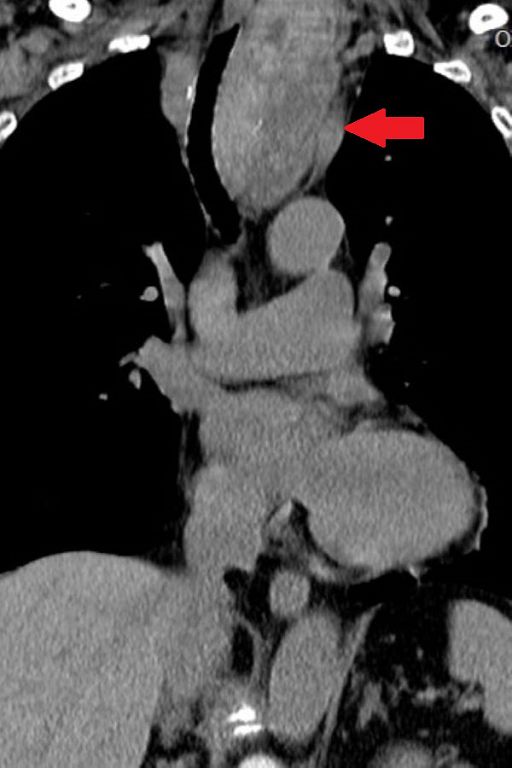

四手聯彈 經鼻經蝶竇腦瘤清除術

傳統手術要取出腦瘤必須開大刀,進行「顱顏切除術」,往往造成病人很大的創傷,復原期既長又外貌受損。花蓮慈院以跨科內視鏡操刀,穿過自然孔道直抵顱底取瘤,病人外表無傷,復原期大幅縮短,讓腦瘤手術從以前 繼續閱讀